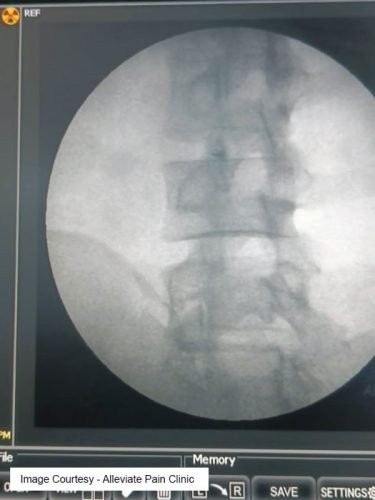

Findings on Investigation: Clinical Diagnosis vs. Imaging

While diagnostic imaging like MRI and CT scans can be valuable tools in assessing spinal conditions, lumbar facet joint pain is often diagnosed clinically. This means that healthcare providers rely on a combination of patient history, physical examination findings, and response to diagnostic injections to confirm the diagnosis.

- Diagnostic Injections : – Facet joint injections involve the injection of local anesthetics and steroids into the suspected facet joint under fluoroscopic guidance. – Pain relief following these injections can provide strong evidence of facet joint involvement and support the diagnosis.

Diagnostic Intrarticular Facet Joint Injection under Fluoroscopy